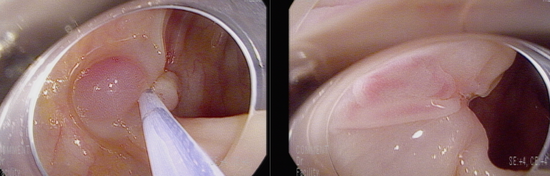

직장에 일부 출혈을 보이는 Vn pit pattern, 중심부 미란성 소견을 동반한 8 mm 크기의 용종 관찰됨.

점막암 이상의 병변을 의심하여 충분히 융기시킨 후 근위부에 snare를 anchor할 hole을 만든 후 충분히 잡아서 육안적 완전 절제함